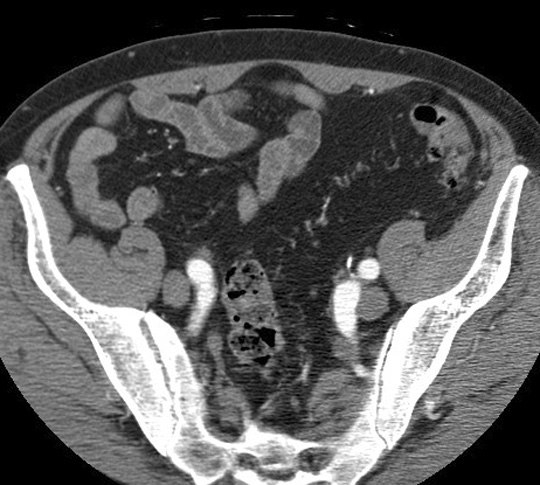

Common iliac vein. Click the image for labeling.